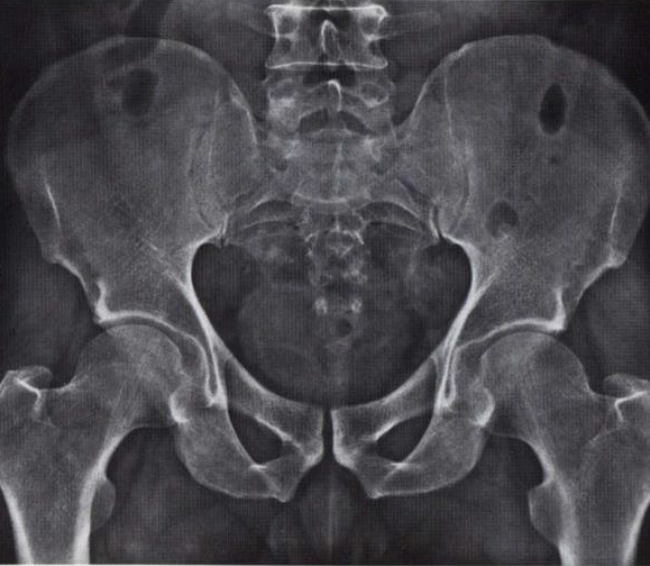

What is this view of the hip? what views are missing?

AP widely collimated

MISSING

Spot AP Hip

Frogleg

Lateral (uncommon due to superimposition)